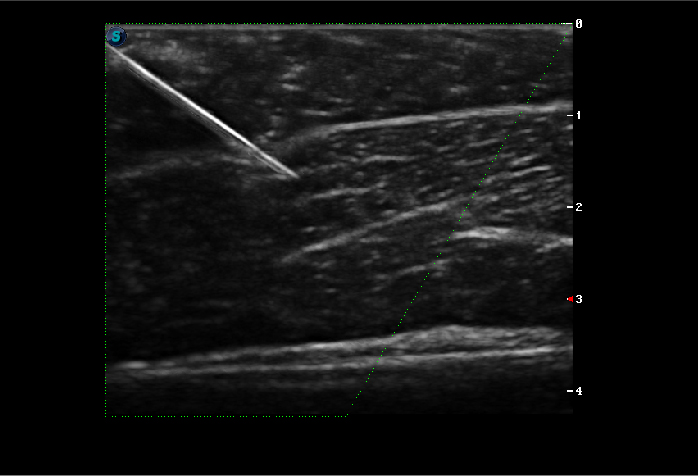

Công nghệ Vis-Needle (Needle Visualization Enhancement): Hỗ trợ nhìn rõ đường kim đâm trong thủ thuật chọc hút tế bào của bác sỹ cơ xương khớp và các bác sỹ châm cứu để tránh tổn thương mô và dây thần kinh.

- Vis-Needle (hỗ trợ nhìn rõ đường kim đâm vào cơ thể), Chế độ B Hình ảnh toàn cảnh, μ-Scan (2D Công nghệ giảm đốm, làm mịn hình ảnh)